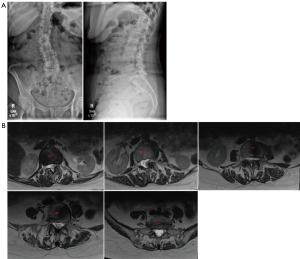

The remainder of the patient’s hospital course was uncomplicated and prior to discharge standing films were obtained and were unremarkable (Figure 4). Patient was discharged to the inpatient rehabilitation unit and she demonstrated improved mental status and full motor and sensory function in bilateral upper and lower extremities with only some mild residual left thigh altered sensation similar to her preoperative baseline. She was admitted to the inpatient rehabilitation unit for 1 week prior to eventual discharge home.

A large right hemicraniotomy was performed and the dura was opened sharply, revealing a large acute SDH. Surgicel was applied to bridging veins emptying into sagittal sinus which were medial edge of the hematoma but which did not appear to be actively bleeding. No obvious active source of hematoma was identified, and brain appeared relaxed and pulsatile following hematoma evacuation. Patient’s surgical incision was closed in the standard fashion. The patient was subsequently transferred to the intensive care unit (ICU). Postoperative drain output days 1–3 were 807, 250, and 0 mL. MRI postoperative day 3 demonstrated an area of possible dural deficiency without pseudomeningocele or large fluid collection over the laminectomy bed (Figure 7). He was placed on flat bedrest, and his drain was placed to gravity and clamped. He was extubated on postoperative day 4 and his subfascial drain was unclamped, was pulled and oversewn.